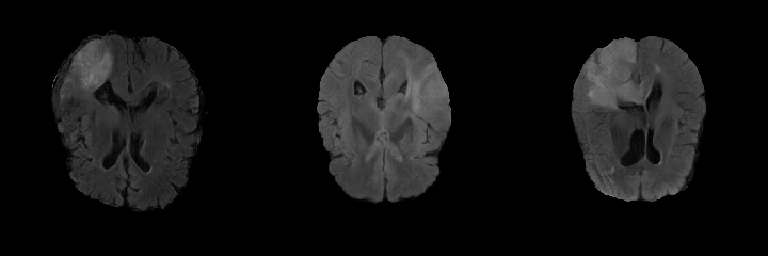

Generated Images Figure 5 shows the generated brain tumor FLAIR samples from -GAN-GP, PGGAN, and PGGAN-SSIM in AXI. The generated samples from all models look realistic and are close to the real images, where the white areas (Gliomas area) are concentrated and unified, indicating the training stability with gradient penalty. However, the samples from -GAN-GP are blurry, and the detailed brain features disappear since the loss of image information becomes serious when the image resolution increases in -GAN-GP. The generated samples from PGGAN and PGGAN-SSIM have clear and realistic brain features (FLAIR texture and tumor appearance) with diversity, which illustrates that PGGAN architecture is a well-suited model to generate brain MR images.